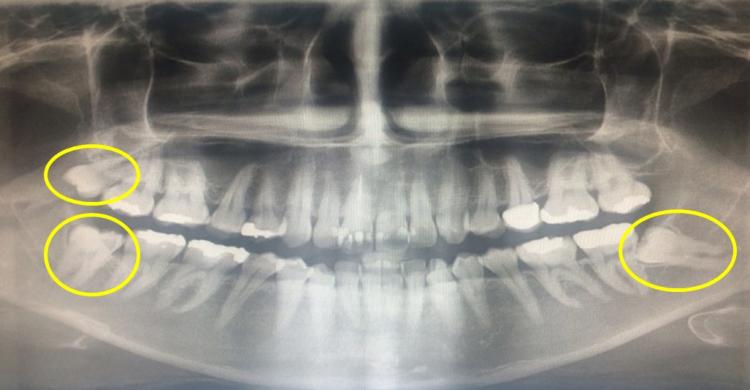

»ç¶û´Ï´Â ¸ÍÃâµÈ À§Ä¡¿¡ µû¶ó ³À̵µ°¡ A ¡æ B ¡æ C ¼øÀ¸·Î ³ª´¶´Ù. È« ±³¼ö´Â ¡°¾Æ·¡ÅÎÀÇ »ç¶û´ÏÀÇ °æ¿ì, ±â¿ï¾îÁø °¢µµ¿¡ µû¶ó ºÐ·ùµÇ´Âµ¥, ±¸° ³»·Î ¶È¹Ù·Î ¸ÍÃâµÅ ÀÖ´Â »ç¶û´Ï ´ÙÀ½À¸·Î ºÎºÐ¸Åº¹, ±Ù½É¿ÏÀü¸Åº¹, ¼öÆò¿ÏÀü¸Åº¹, ¿ø½É¿ÏÀü¸Åº¹ ¼øÀ¸·Î ¹ßÄ¡Çϱ⠾î·Á¿öÁø´Ù¡±¸ç ¡°À§ÂÊ »ç¶û´ÏÀÇ °æ¿ì Ãß°¡·Î »ó¾Çµ¿(À§ÅλÀ ¼ÓÀÇ ºñ¾îÀÖ´Â °ø°£)°ú ´ê´Â Á¤µµ¿¡ µû¶ó ³À̵µ°¡ ´Þ¶óÁö¸ç »ó¾Çµ¿°ú ´êÁö ¾Ê°í ³ª¿Í ÀÖ´Â °æ¿ì »ç¶û´Ï ¹ßÄ¡¿¡ °¡Àå ¼ö¿ùÇÏ´Ù¡±°í ¼³¸íÇß´Ù.